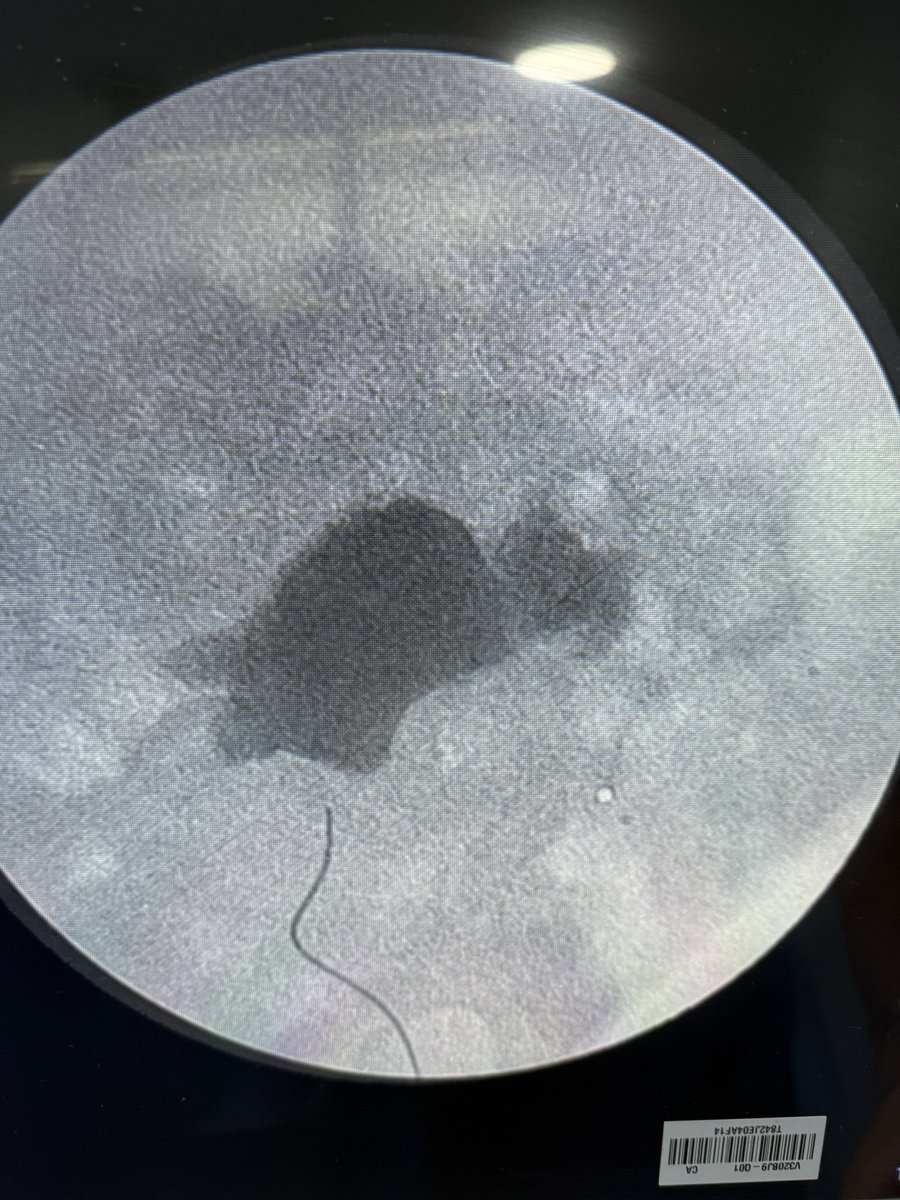

💥 Our Hands-On Course on Ultrasound-Guided PCNL at @CMUN_Urologia was a great success!

An incredible day of practical learning, experience sharing, and passion for advancing minimally invasive surgery